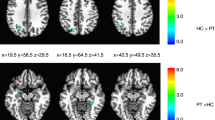

Between-group analysis of PATpre against CONTR revealed significantly increased functional activity in the contralateral S1 during left hand/face (V2, Ha) and right face (V1, V2) stimulation, and in the contralateral S2 during right face (V1, V2) stimulation (Table 1, Fig. 1). Further areas of increased contralateral parietal activity in these conditions encompassed the intraparietal sulcus, supramarginal gyrus or superior parietal lobe. Besides enhanced S2 activation, right face stimulation (V1, V2) induced increased temporal activity in the left-hemispheric superior temporal gyrus (STG). Enhanced contralateral insular activity was observed after both left- (V2) and right-sided (V1) stimulus application to the face. Within the frontal lobe, enhanced right ventral (pre)motor (M1/PMv) was seen during left face stimulation (V2), and was visible as trend also in the other conditions in the hemisphere contralateral to stimulation where it did not survive adjustment for the number of conditions (see table s-1 for trends). Post-hoc evaluation of functional activity changes in these conditions before and after BoNT-A within patients did not yield significant differences.

Areas with significantly increased activity in patients with ADSD. The middle column shows differential activation (color coded for each body region) projected on the respective contralateral hemisphere of the participants’ 3D-reconstructed average brain. In the lateral columns, increased activity in in selected areas (top to bottom: S1/superior parietal lobe, S2, insular/temporal cortex) is projected on axial slices of the averaged brain. The overlaid statistical parametric maps were thresholded at pFWEc < 0.0083 and a cluster-forming threshold of p < 0.001 uncorrected. Slice position in MNI space in mm is given relative to the anterior commissure (above +; below −). CONTR, healthy control participants; PATpre, ADSD patients before botulinum toxin A treatment; Ha, dorsal hand; V1, forehead; V2, upper lip, L/R, left/right hemisphere.